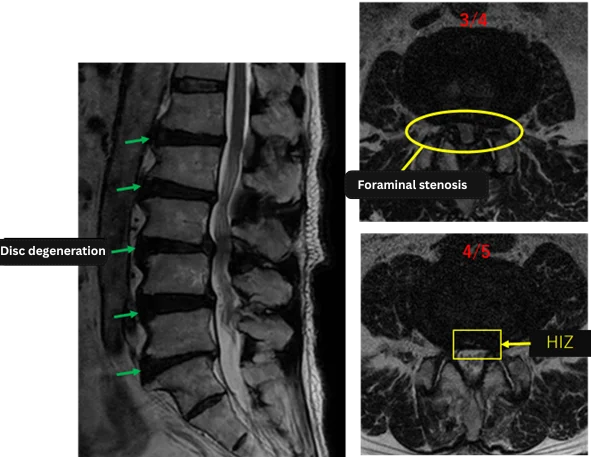

| Level | Findings |

| L1/2 | Degeneration |

| L2/3 | Degeneration, bulging |

| L3/4 | Degeneration, bulging, spinal canal stenosis, left foraminal stenosis, endplate degeneration |

| L4/5 | Degeneration, bulging, annulus fibrosus tear, left foraminal stenosis |

| L5/S | Degeneration, bulging, reduced disc height |

The above findings were also observed on the imaging.

Stenosis of the spinal canal and foramina, annular fissure, disc degeneration, and endplate degeneration at L3/4, L4/5, and L5/S were considered highly likely to be the cause of the patient’s primary symptoms.